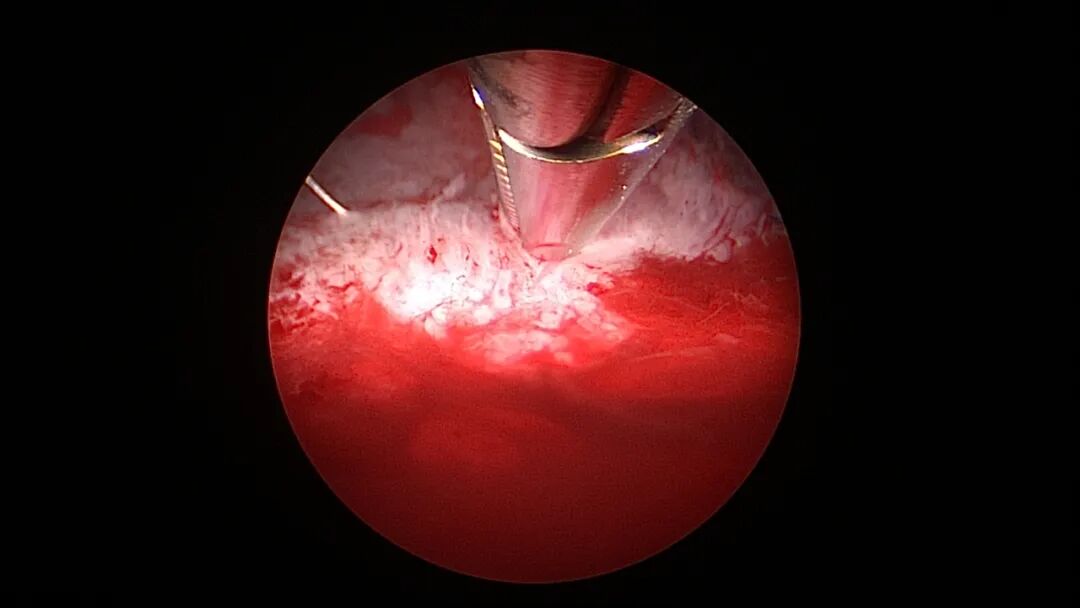

单级电针标记挂钩位置